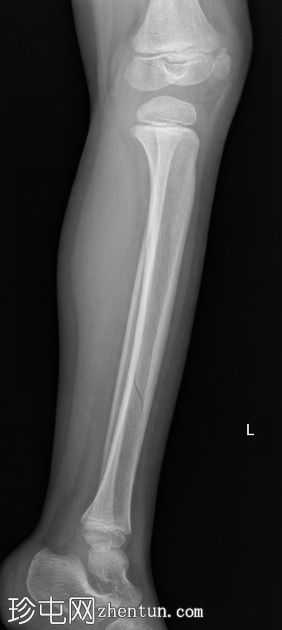

左腿及踝关节

X线片

侧位

胫骨远端骨干可见一条螺旋状透亮线,提示骨折(正位、侧位)。

应用锐化算法并放大正位片(骨折由近端向远端)和侧位片。

幼儿骨折是指幼儿因扭转(足部着地时股骨内旋)导致的胫骨中远端轻微移位的螺旋状骨折,这种情况可能发生在儿童绊倒时。患者接受了6周的石膏外固定治疗。

请注意,应用锐化骨算法并放大图像后,骨折及其范围会更加清晰可见。